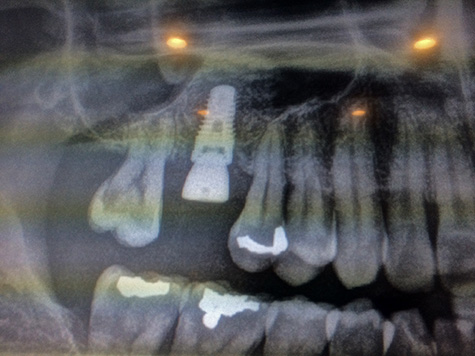

back in the operating room, we looked at the x-ray. now instead of an empty gap was the silhouette of the dental implant. i now officially join the ranks of metahumans in being part flesh and part metal! when i asked the doctor if it was a titanium implant, he said no, but something even better, even though he didn't say what it was. the operation was a complete success, no complications whatsoever. my sinus cavity was intact, just pushed up a little bit to make room for the additional bone graft. my right nostril felt stuffed up, the doctor said this was normal after a sinus lift (it cleared up soon after i left). he said that my jawbone was the optimal hardness level (scoring 35 on this fancy bone hardness meter), so the implant is extremely stable.

my next appointment will be in 4-6 months. the dental implant right now has a temporary healing abutment, to keep the healing flesh from covering over the exposed nub. the next time i come back, he will simply unscrew that and screw in the permanent abutment, no surgery required. however, as a precaution, i'm to come in next friday for a quick check-up, to make sure everything is healing okay. not even to take out the sutures, which will disappear on there own. the doctor also gave me his cell phone number in case of an emergency. so how much was the bill? $2800! i was a bit shocked, because i thought it'd be $1900. i asked for a copy of the invoice: $1950 for the dental implant ("surgical implant body: endosteal"), but an additional $850 for the sinus lift ("sinus augmentation with bone or subst"). the doctor was flexible with the payment, said i could pay however much i wanted today; i decided to pay half now, and pay the other half in 4-6 months. i still need to pay another $800 for the actual crown. he wrote out a few prescriptions: i still had a bottle of unused hydrocodone, so he printed a slip for prescription-strength motrin (which i found out is just 600mg ibuprofen) and some amoxicillin/clavulanic acid. as a parting gift, he gave me a little ice pack for my cheek. the whole sinus lift/dental implant procedure from start to finish took about an hour.